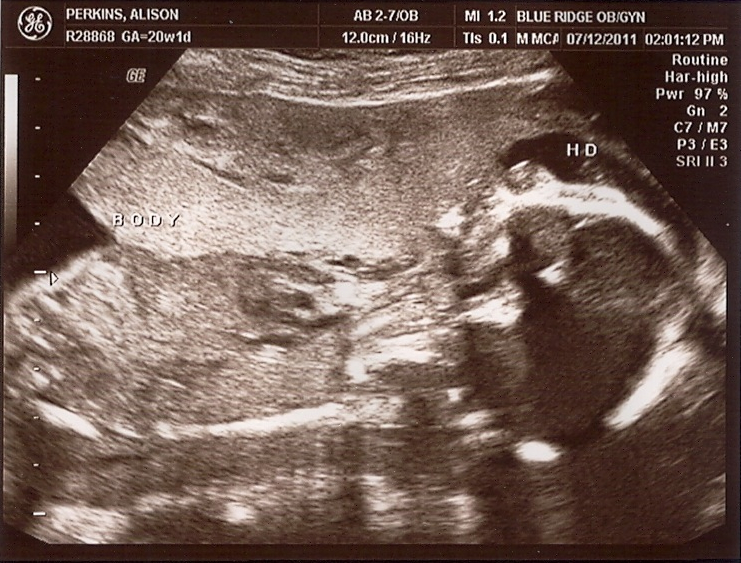

20-week Ultrasound